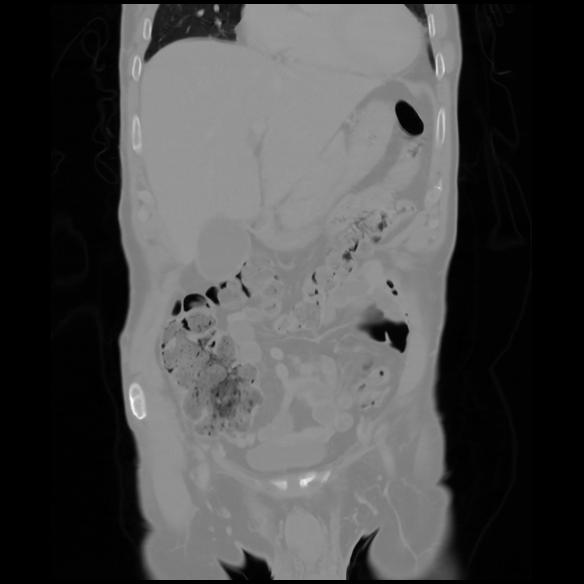

6 CUERPO,CE,Coronal,3.000,CUERPO,Coronal,